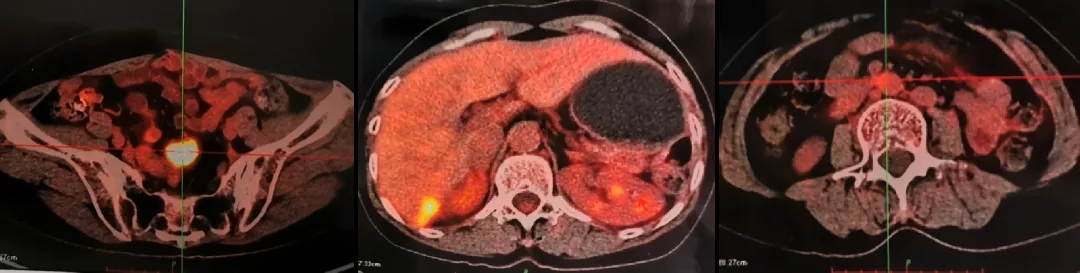

2013.5.10 PET-CT:肝肾隐窝、脾肾间隙、脾门旁、腹膜后可见斑片状、囊实性及结节状影,实质部分FDG代谢增高,考虑转移。

2013.5.10 PET-CT检查结果

2016.10.14查PET-CT: 盆腔内软组织密度灶,FDG代谢异常增高,考虑转移灶;右肝后下段包膜处结节样、片状转移灶;左肾前方斑片状,腹主动脉管壁处(L3椎体水平)FDG代谢轻度增高,考虑肿瘤活性组织存在。

PET-CT检查结果